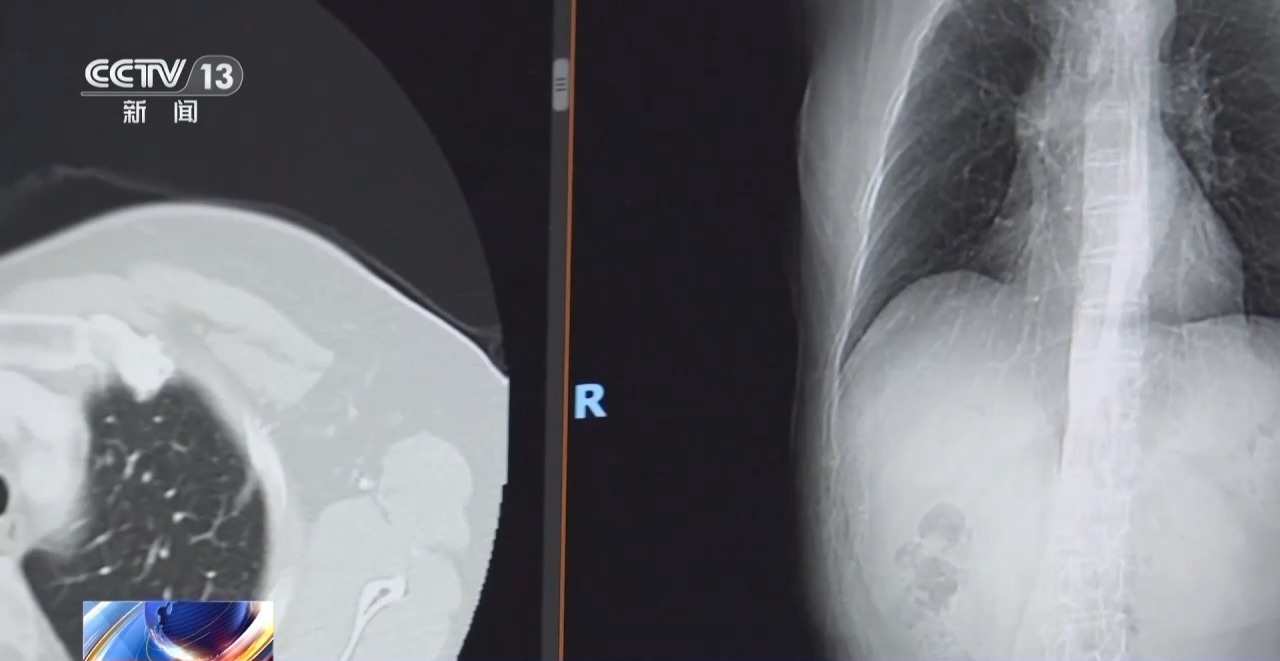

今天至4月21日是第31个世界肿瘤防治宣传周,世界卫生组织下属的外洋癌症研究机构(IARC)最新数据显露:肺癌当今是全球发病率和死一火率均排行第一的癌症波多野结衣电影,肺癌纠合十年位居全球癌症死一火率首位。

北京大学肿瘤病院胸外一科主任 陈克能:把柄国度癌症中心最新公布的数据,2022年,我国新发肺癌的病例越过106万,死一火数越过73万,发病率和死一火率齐占恶性肿瘤的第一位。

从全球范围来看,肺癌的发病在这10年还是握续增高的,死一火率10年一直是排第一位的,可能跟咱们当今的生活节拍增快、工业化水平提高、压力增多、吸烟东谈主数在发展中国度递加的原因是有一定的干系的。

北京大学肿瘤病院胸外一科主任 陈克能:全球把这种磨玻璃样小结节的肺癌,混同于正本传统的肺癌,这是要不得的。磨玻璃样结节的肺癌跟传统的肺癌,其实它的转归预后不是一趟事,浮浅说它是一个相配懒惰的“懒”癌。

跟着我国医学高出,肺癌患者的养息有显然冲突,磨玻璃样结节的肺癌,5~10年的生涯率接近百分之百,实性肿块一期肺癌的5年生涯率约为70%~80%。